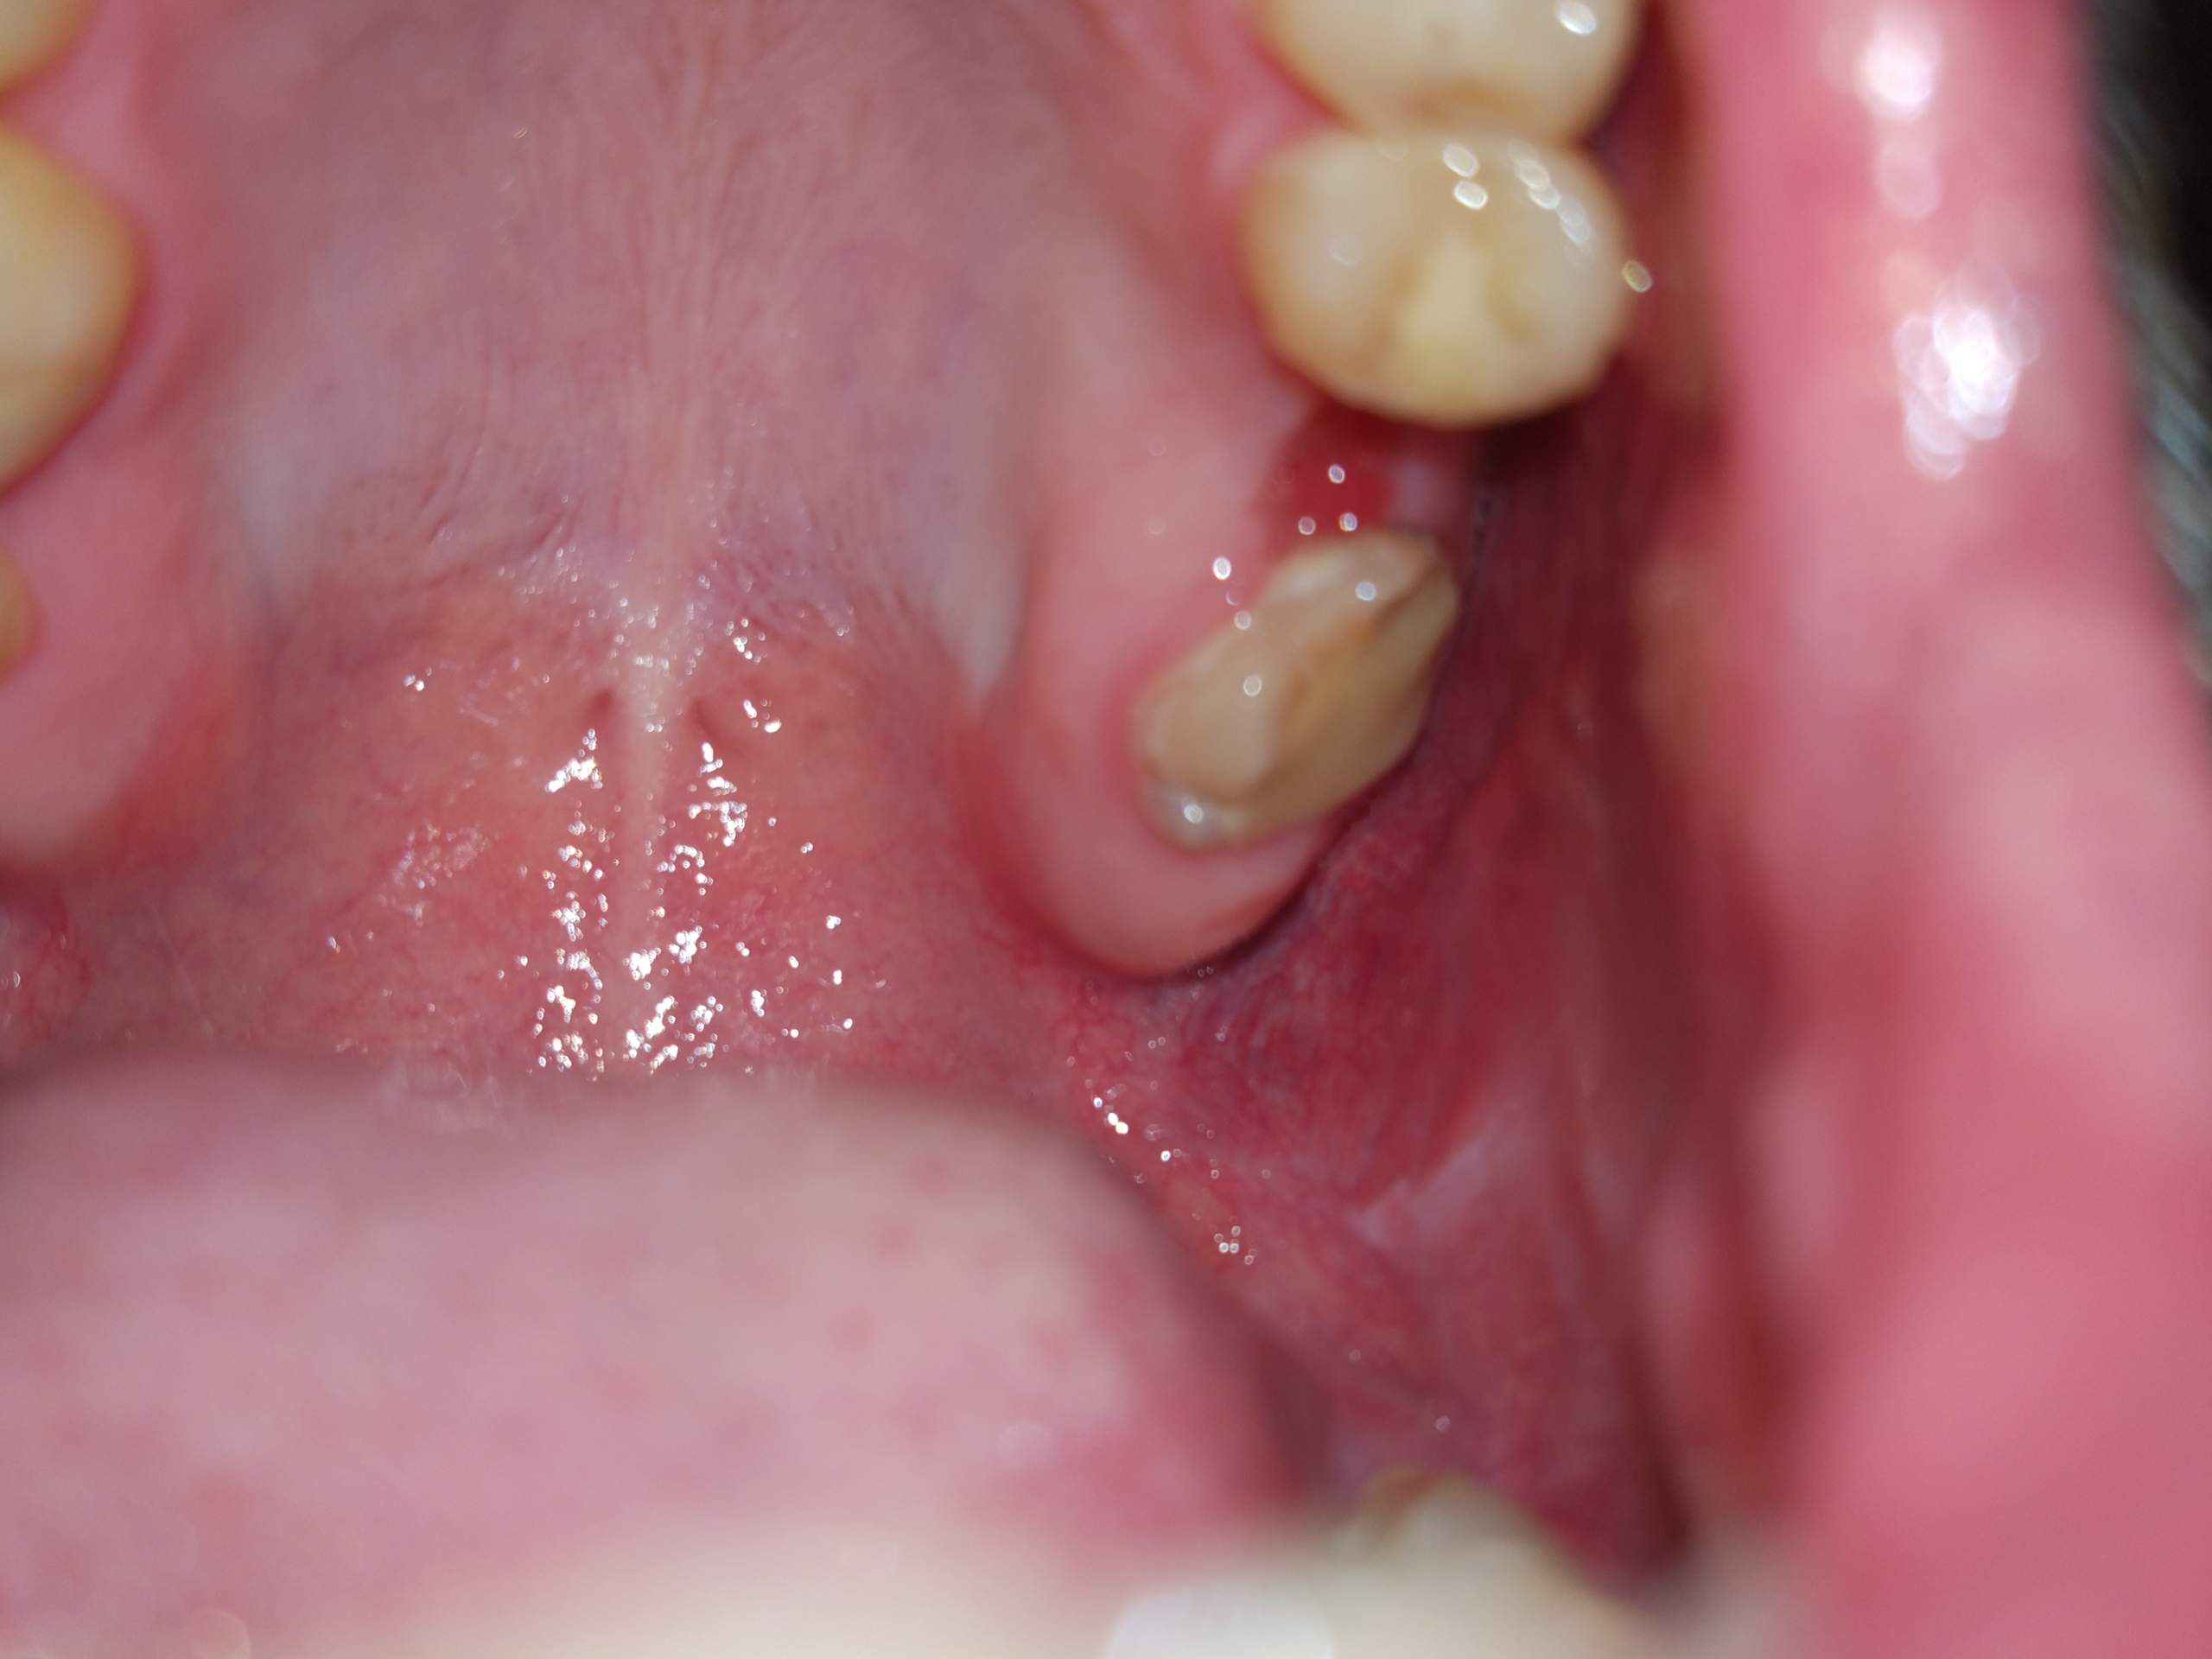

Neben der Kieferhöhleneröffnung im Rahmen von Extraktionen kann diese vor allem auch im Rahmen von Wurzelspitzenresektionen vorkommen. Welche Behandlung ist erforderlich wenn die Kieferhöhle zum Mund hin offen ist z. Nach der Extraktion eines verdächtigen Zahnes wird ein Nasenblastest durchgeführt.

Durch das Vernähen der Wunde schließt der Zahnarzt den offenen Kieferknochen und verringert die Wundoberfläche. Dies geschieht mittels Abtasten der Alveole mit einer Knopfsonde oder durch den Nasenblasversuch.

Hallo wer hat erfahrung mit eröffneter kieferhöhle nach einer zahnextraktion. Also es strömt jedenfalls von nase luft in den mund und umgekehrt. Auch an eine ungewollte Eröffnung der Kieferhöhle durch den Arzt muss gedacht werden. In die Öffnung fließt Blut bildet sich zu einem Blutgerinnsel und innerhalb von drei Monaten zu einem Faserknochen. Nach Eröffnung einer gesunden Kieferhöhle besteht die Gefahr dass über die MAV durch aszendierende Infektion. Welche Hausmittel helfen bei einer Kieferhöhlenentzündung. Sollte wider Erwarten nach einer Zahnextraktion in der Kieferhöhle eine Nachblutung auftreten so legen Sie einen Tupfer oder ein sauber geknotetes Taschentuch auf die Wunde und beißen so zu dass die Wunde komprimiert wird. Der Patient bläst in seine Nase wie beim Schnäuzen hält sich dabei die Nase luftdicht zu. Vermeiden Sie bitte Niesen oder kräftiges Schnauben beim Naseputzen um erhöhten Innendruck der Kieferhöhle zu vermeiden.